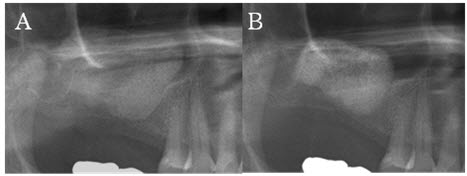

| »ó¾Ç ¿ìÃø »ó¾Çµ¿¿¡ Ãø¹æÁ¢±Ù¹ýÀ¸·Î ÀÌ½ÄµÈ BHA. »ó¾Çµ¿ °ñÀ̽ļú Á÷ÈÄ(ÁÂ)¿Í 6°³¿ù ÈÄ(¿ì)ÀÇ ¼Ò°ß |

| »ó¾Çµ¿ °ñÀÌ½Ä 6°³¿ù ÈÄÀÇ Á¶Á÷¼Ò°ß. bovine hydroxyapatite(BHA)°¡ ¶Ñ·ÇÇÏ°Ô º¸À̰í À̽ÄÀç ÁÖÀ§·Î ½Å»ýÃþÆÇ°ñ(lamella bone, È»ìÇ¥)ÀÌ º¸ÀδÙ. |